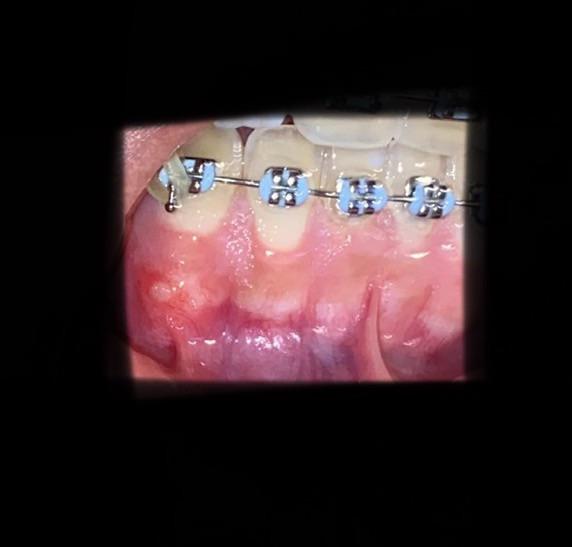

Bump On Gum With Braces . A dentist may prescribe antibiotics,. A dental abscess is a collection of pus that forms around the roots of a tooth or in the gums. Braces create numerous nooks and. There are two main types, periapical abscess, which starts inside the tooth and. Treatment depends on the cause. If your gums swell after your braces are installed or adjusted, the symptoms may disappear after a few days. It boils down to thoroughly removing all plaque biofilm from your gumlines around each bracket in your mouth. How to get rid of swollen gums with braces. Swollen gums with braces are completely preventable 99% of the time. It forms when bacteria build up and cause infection, causing pain, swelling, and other symptoms. Bumps on the gums can occur for many reasons, such as tooth decay, oral fibroma, and, in rare cases, mouth cancer.

Your Braces Could Be Causing Gum Problems Gum Swelling Due To Braces Bump On Gum With Braces If your gums swell after your braces are installed or adjusted, the symptoms may disappear after a few days. How to get rid of swollen gums with braces. Bumps on the gums can occur for many reasons, such as tooth decay, oral fibroma, and, in rare cases, mouth cancer. It boils down to thoroughly removing all plaque biofilm from your. Bump On Gum With Braces.